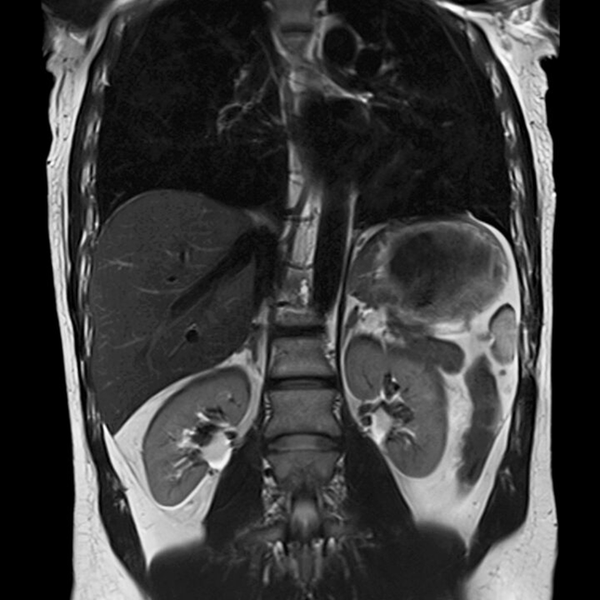

Магнитно-резонансная томография брюшной полости + МР холангиография с контрастированием – важный метод исследования с введением контрастного вещества, который позволяет визуализировать печень, почки, надпочечники, селезенку, желчный пузырь, поджелудочную железу, верхние отделы надпочечников, лимфатические узлы, желчные протоки.